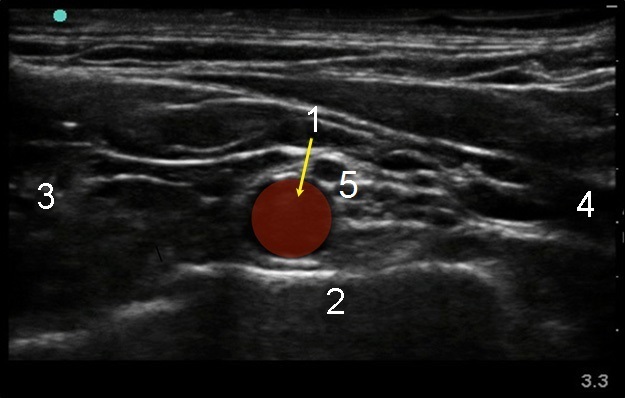

1. Supraclavicular Artery

2. 1st Rib

3. Medial

4. Lateral

5. Brachial Plexus